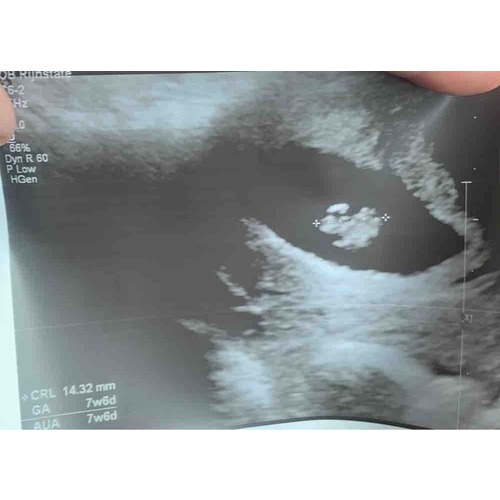

Mijn echo, denk zelf 7w6d maar meting zei 7w1d

Vandaag echo gehad! 7 weken 6 dagen 🥰